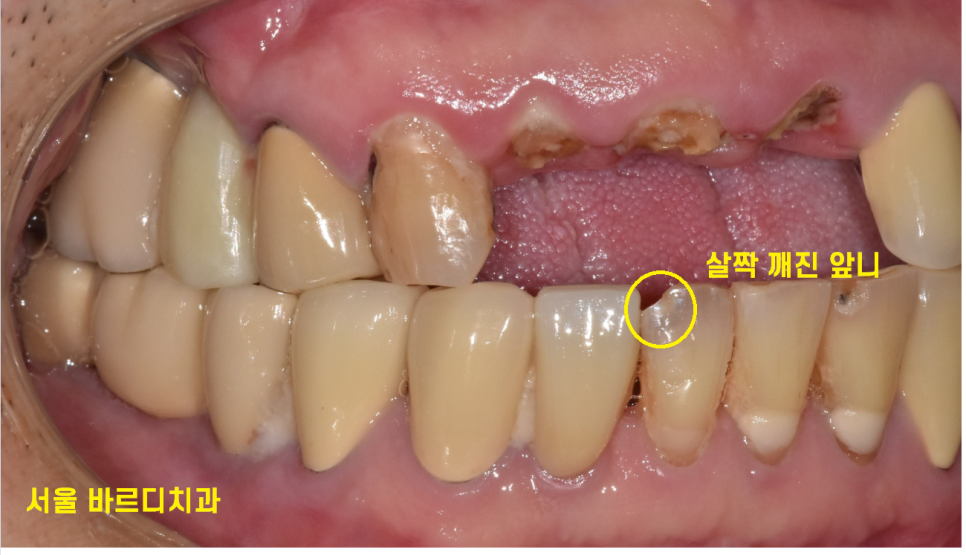

다른 치아, 입술에 문제가 없는지 1차적으로 확인

아래 앞니도 살짝 깨져있네요~

이건 큰 문제가 아니고

오늘 환자분은 이미 치료한 치아가 많아

브릿지를 할 수 없는 상황입니다.

양 옆에 딱 1개만 자연 치아이고

전부 보철이었거든요~

이럴 경우 뽑고 임플란트로 대체하는 것이

가장 좋은 치료방법입니다.